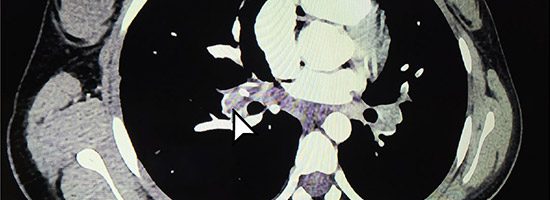

Dos investigadoras de la Universidad CES realizaron importante estudio clínico, sobre una patología poco frecuente en pacientes pediátricos con tuberculosis.